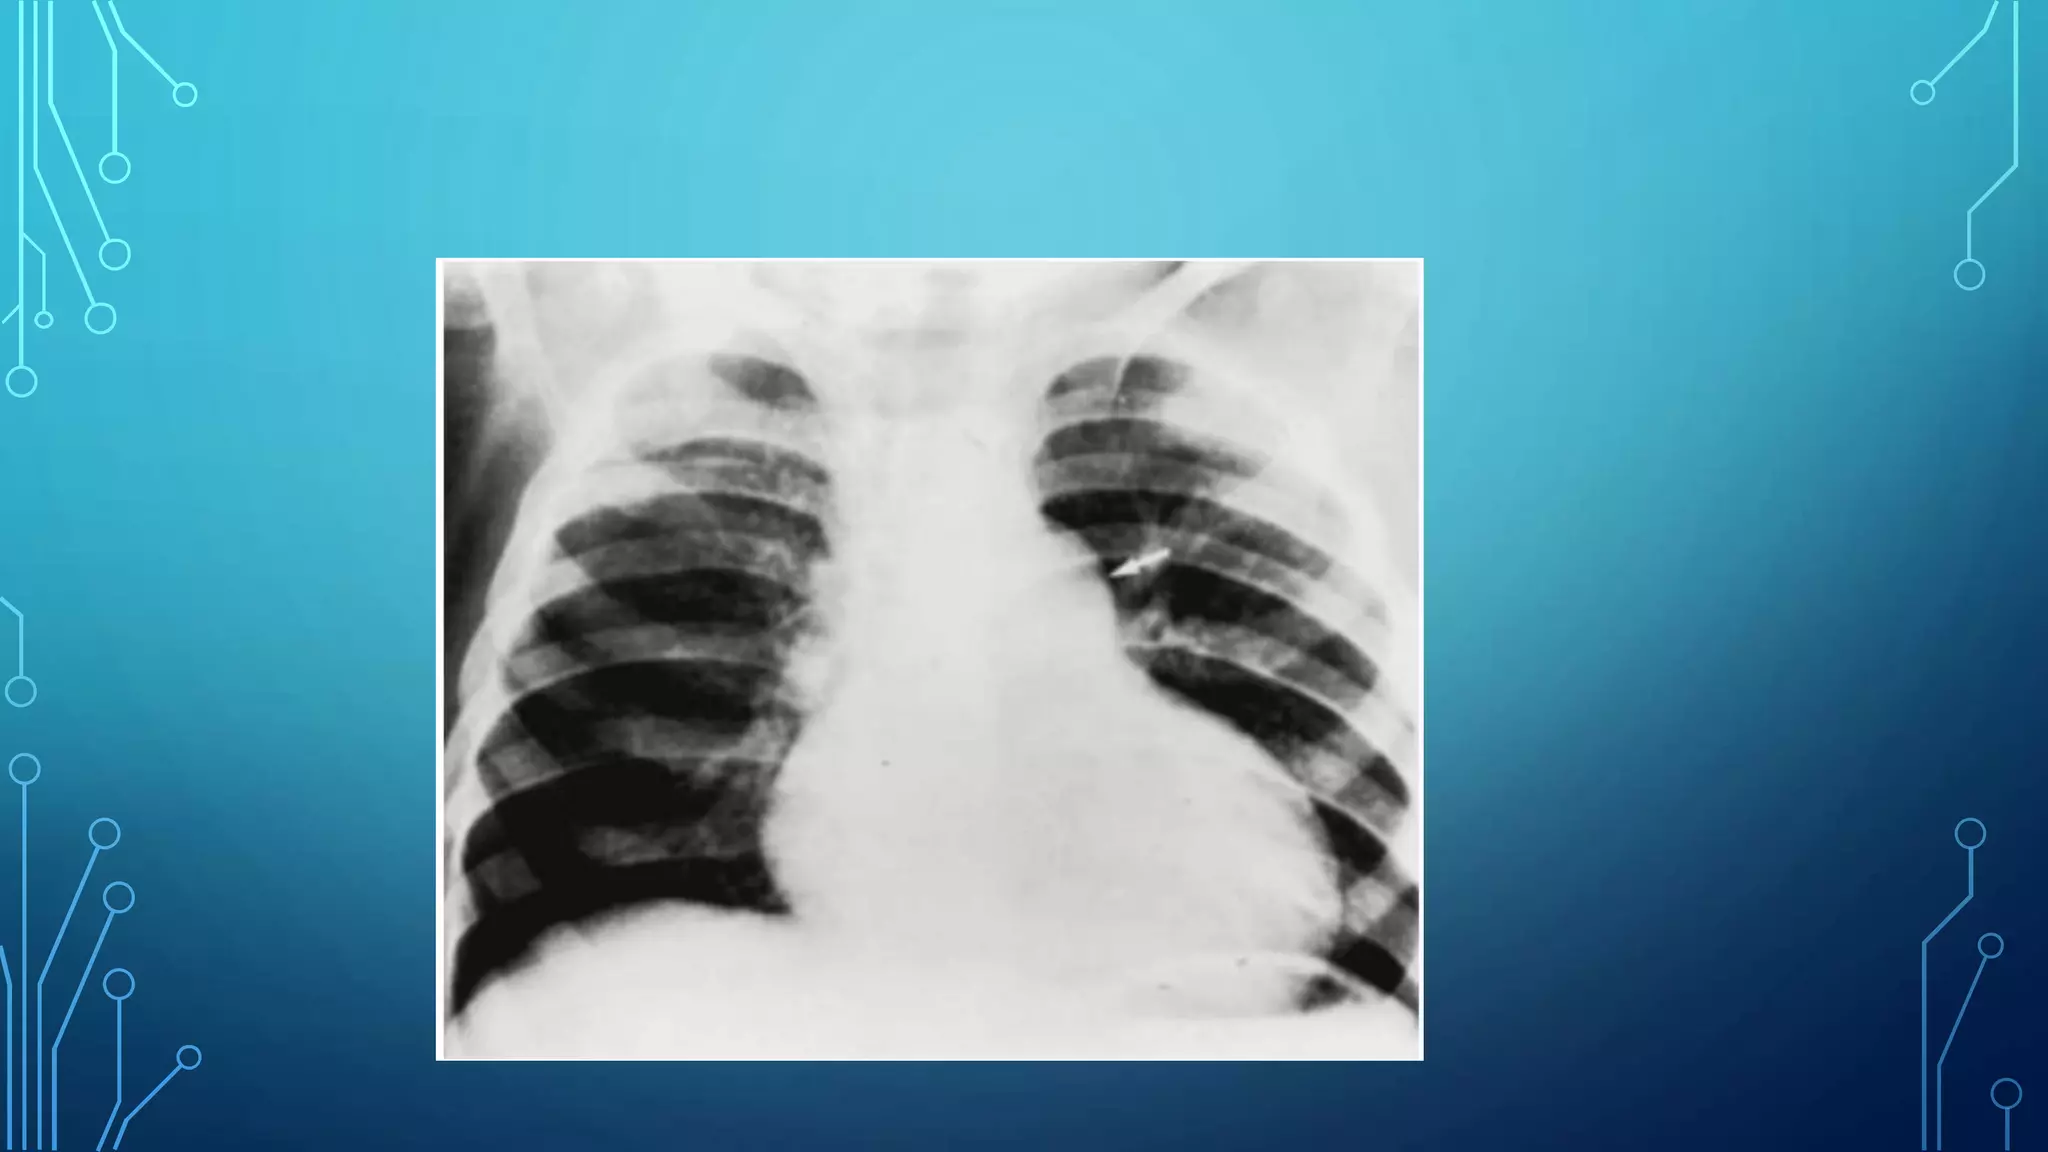

Radiography

• Heart size is usually normal, but the main PA segment may be

prominent with valvular stenosis (caused by poststenotic dilatation).

Cardiomegaly is present only if CHF develops.

• Pulmonary vascular markings are usually normal but may decrease

with severe PS.

• In neonates with critical PS, lung fields are oligemic with a varying

degree of cardiomegaly.